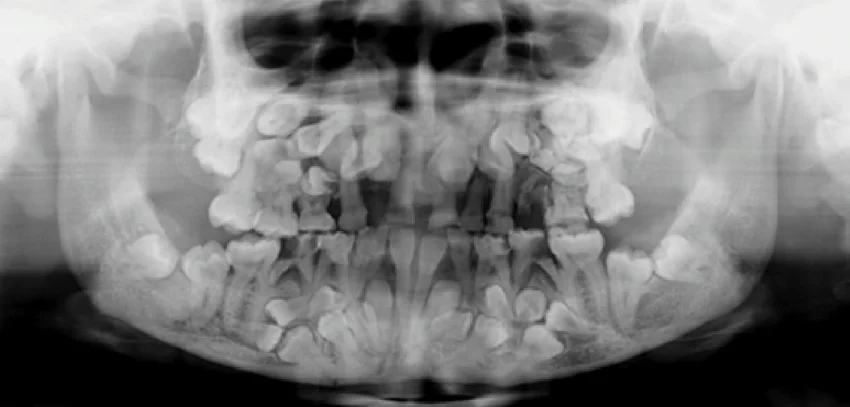

Зубы необходимы для пережевывания еды до консистенции, пригодной для последующей переработки системой ЖКТ. Многие люди считают, что у человека должно быть 32 зубной единицы. Но это не так. В сети можно увидеть статьи, рассказывающие об особенностях строения челюсти. В норме бывает от 28 до 32 зубных единиц, так как не у всех вырастают зубы мудрости.

Зубная единица состоит из нескольких частей: корень, шейка, коронка и пульпа. С помощью корней зубы фиксируются в альвеолярных тканях. Корневые системы различаются в зависимости от нагрузки. Например, строение крупных корней у моляров. Шейка расположена между коронковой частью и корневой системой, ниже краев эмали. Сверху она покрыта эмалью. Внутренняя область называется пульпой: она расположена в пульповой камере и зубных каналах, а также окружена дентином.

• Временные. Это молочные зубы, которые прорезались у малыша. Первый комплект прорезывается, когда ребенок питается грудным молоком. Их анатомия практически не отличается от постоянных. Отличий всего три: маленький размер из-за небольших объемов детской челюсти, минимальная насыщенность тканей минеральными веществами, укороченная корневая система.

• Постоянные. Коренные зубы сменяют молочные. Они имеют более сильную корневую систему, но при выпадении придется пользоваться услугами имплантации и протезирования.

• Зубы мудрости. Располагаются в самой удаленной области челюсти. Третьи моляры прорезываются в возрасте от 18 до 25 лет и часто требуют удаления, так как становятся причиной многих проблем. Они растут не у всех, поэтому многие люди имеют 28 зубов.

Иногда у ребенка или взрослого человека встречается аномальное количество зубов. Например, в челюстном аппарате могут отсутствовать зародыши нескольких или всех зубных единиц. Иногда зародыши погибают по разным причинам. Это может произойти в результате различных заболеваний, перенесенных мамой во время беременности. Могут сказаться и патологии, которые перенес ребенок в первые годы. В таком случае у человека будет меньше зубных единиц, чем это принято нормой.

Встречаются случаи со сверхкомплектом единиц. Например, у пациента появляются лишние премоляры или клыки. В таком случае врач может обнаружить 34 или 36 зубных единиц. Доктор может рекомендовать удалить дополнительные отростки, так как они могут испортить прикус. У 3% населения планеты обнаруживается 1 лишний зуб.